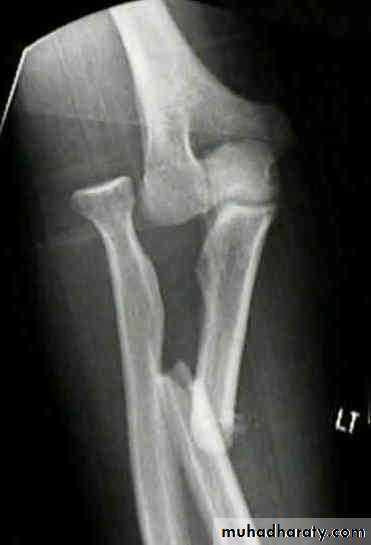

Monteggia fracture dislocation of the ulna

It is fracture of the proximal third of the ulna with dislocation or subluxation of the proximal radio- ulnar joint .

X-ray : in isolated fracture ulna it is essential to take true a-p and lateral views of

the elbow ; the normal radial head is usually pointing to wards the capitulum in

monteggia it is not ; in addition to appearance of the fracture .

Montegia fracture dislocation